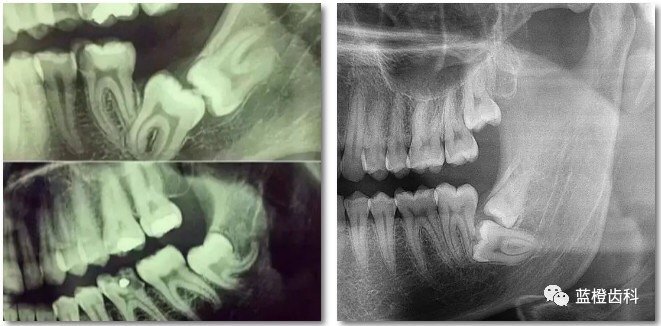

很多人都這樣覺得:看大病拍片我還能理解,看個(gè)牙齒也要拍啊?沒必要吧,而且有輻射,對身體也不好。 看牙為什么要拍片? 先放幾張圖,讓你們漲漲姿勢,不拍片根本不知道你的牙齒長得會(huì)有多奇葩! 從下圖中可以知道除了外層的一點(diǎn)牙釉質(zhì),牙齒里面出了問題,肉眼是無法觀察到的。牙醫(yī)不長透視眼當(dāng)然不能透過現(xiàn)象看到牙齒本質(zhì)嘍。因此,為了對牙齒進(jìn)行全面的了解,拍個(gè)牙片還是很有必要的。 圈出來的地方或多或少都有點(diǎn)齲齒,但是有些你并不能看見。這些齲齒還淺不會(huì)讓你有什么感覺,頂多吃東西塞牙,和冷水敏感而已。 暗的部位說明齲齒已經(jīng)非常嚴(yán)重了! 下面這個(gè)是接近牙髓了: 牙齒的牙根是埋在牙槽骨中的,醫(yī)生沒有透視眼,為了解患牙的牙根的形態(tài)、走向、長度及根尖周有無病變及病變大小,或者懷疑有肉眼無法確認(rèn)的其它牙科問題,都會(huì)建議患者去牙科的X光,甚至,口腔CT來全面性地確認(rèn)問題,以制定合適的治療計(jì)劃。 拍牙片的輻射劑量有多大? 人體接觸X線有一定的潛在的損害,依照目前國際放射防護(hù)委員會(huì)的推薦,一般民眾輻射限值為每人每年不得超過5毫西弗(mSv)=(5000微西弗 (μSv))。 其實(shí),我們每時(shí)每刻都生活在電磁輻射中。我們生活中所接受到的大部分的輻射(約85%)是來源于自然環(huán)境的,如太陽、土壤等。來源于醫(yī)療診斷與治療的輻射量占14%左右。 美國牙醫(yī)協(xié)會(huì)也給出數(shù)據(jù),在醫(yī)療輻射中,來源于牙科的輻射僅占到約2.5%。關(guān)于牙科放射量,兒童放射學(xué)會(huì)給出更為清晰的對比:拍一張曲面平展的輻射量,相當(dāng)于約3天的自然環(huán)境輻射量;4張牙合翼片的輻射相當(dāng)于約0.6天的自然環(huán)境輻射量??傊难榔妮椛淞科鋵?shí)是較小,大家不用擔(dān)心。 牙片對于口腔疾病的診斷尤為重要,且輻射量很小,所以只要有必要,大家不要排斥拍片診斷。 孕婦和兒童可以拍牙片嗎? 在某些口腔疾病治療的緊急狀況下,孕婦可能不得不在寶寶出生前拍牙片,因?yàn)槲唇?jīng)治療的牙科感染會(huì)構(gòu)成胎兒的潛在威脅。一般不主張?jiān)袐D在懷孕初期(前三月)拍牙片,畢竟胎兒比正常人更嬌嫩更敏感。孕期三個(gè)月過后,如孕婦必須接受X光拍攝時(shí),可以穿防護(hù)服(鉛衣)以防放射線危害孕婦及胎兒。只要不是直接對準(zhǔn)腹部或其附近部位的高劑量輻射,對胎兒的影響幾乎微不足道,準(zhǔn)媽媽們不必過于擔(dān)心。此外,兒童在拍牙片時(shí)都會(huì)采用低劑量、以最優(yōu)化的劑量達(dá)到臨床要求,同時(shí)進(jìn)行必要的防護(hù),大人們也可以不必再糾結(jié)于孩子的輻射傷害。 牙片(牙科X光)有助于牙醫(yī)直接觀察到普通口腔檢查難以發(fā)現(xiàn)的牙齒和牙周組織問題,是早發(fā)現(xiàn)早治療口腔問題的關(guān)鍵。希望大家一定要認(rèn)識(shí)到牙片的重要性,拍片沒有很大的風(fēng)險(xiǎn),大家不要擔(dān)心!